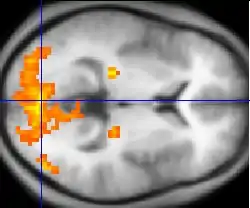

Hallazgos de neuroimagen

Ciertos estudios que utilizaron pruebas neuropsicológicas y de neuroimagen, tales como las tecnologías de imagen por resonancia magnética funcional (IRMf) y la tomografía por emisión de positrones (TEP) para examinar las diferencias funcionales en la actividad cerebral, demostraron que las diferencias parecen ocurrir más comúnmente en los lóbulos frontales, hipocampo y lóbulos temporales,[178] vinculados al déficit neurocognitivo que a menudo se asocia con la esquizofrenia.[179] Los trastornos del lenguaje, de la atención, el pensamiento abstracto, el juicio social y la planificación de acciones futuras, todos característicos en la esquizofrenia, están íntimamente ligados a las funciones del lóbulo frontal.

También se ha reportado cambios en la estructura microscópica del lóbulo temporal de esquizofrénicos.[184] Un metaanálisis del 2009 de estudios de imágenes de resonancia por difusión, identificó dos lugares coherentes de reducción de la anisotropía fraccional en la esquizofrenia. Una región, en el lóbulo frontal izquierdo, es atravesada por vías provenientes de la materia blanca con interconexión hacia el lóbulo frontal, tálamo y giro cingulado; la segunda región en el lóbulo temporal es atravesada por vías de interconexión de la materia blanca hacia el lóbulo frontal, ínsula, hipocampo, amígdala, lóbulo temporal y occipital. Los autores sugieren que dos redes de interconexiones por parte de la materia blanca pueden verse afectadas en la esquizofrenia, con una probable «desconexión» de las regiones de materia gris que enlazan.[185] Mediante estudios de imagen por resonancia magnética funcional (IRMf) se ha demostrado que hay una mayor conectividad en el cerebro de pacientes esquizofrénicos en la red de neuronas encargadas de la actividad cerebral cuando el sujeto no está enfocado en el mundo exterior, así como de la red de atención dorsal encargada de los sistemas de orientación sensorial, y puede reflejar la excesiva orientación hacia la atención introspectiva y extrospectiva, respectivamente. La lucha contra la mayor correlación entre las dos redes sugiere excesiva rivalidad entre dichas interconexiones.[186] Por su parte, los síntomas positivos alucinativos, los delirios y el trastorno del pensamiento están asociados con una disfunción del lóbulo temporal o de las estructuras que conforman el sistema límbico como la amígdala y el hipocampo.